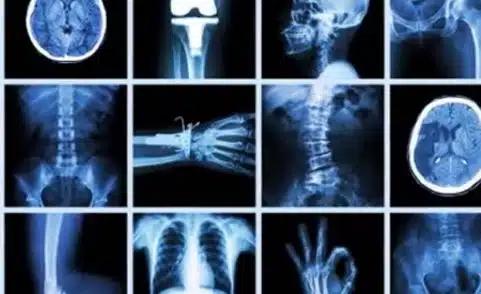

Posted In: X-ray

Posted In: CT, MRI, Ultrasound, X-ray

Posted In: CT, Injections & Biopsies, MRI, X-ray